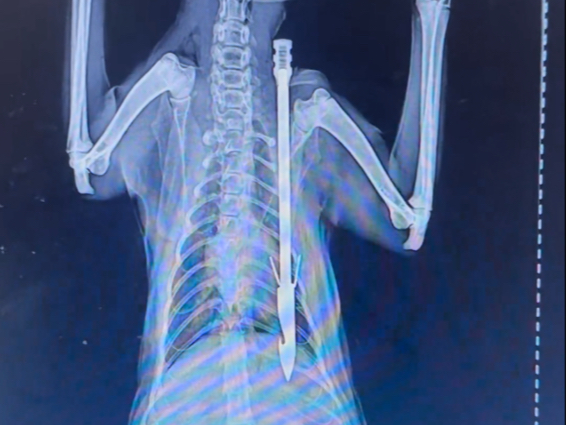

被射了一箭的小灰

59

该视频暂无简介

热度: 663